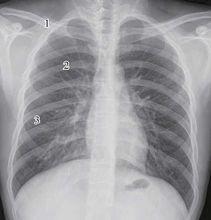

肋骨的解剖1、肋頭costal head

2、肋結節costal tubercle

3、肋溝costal groove